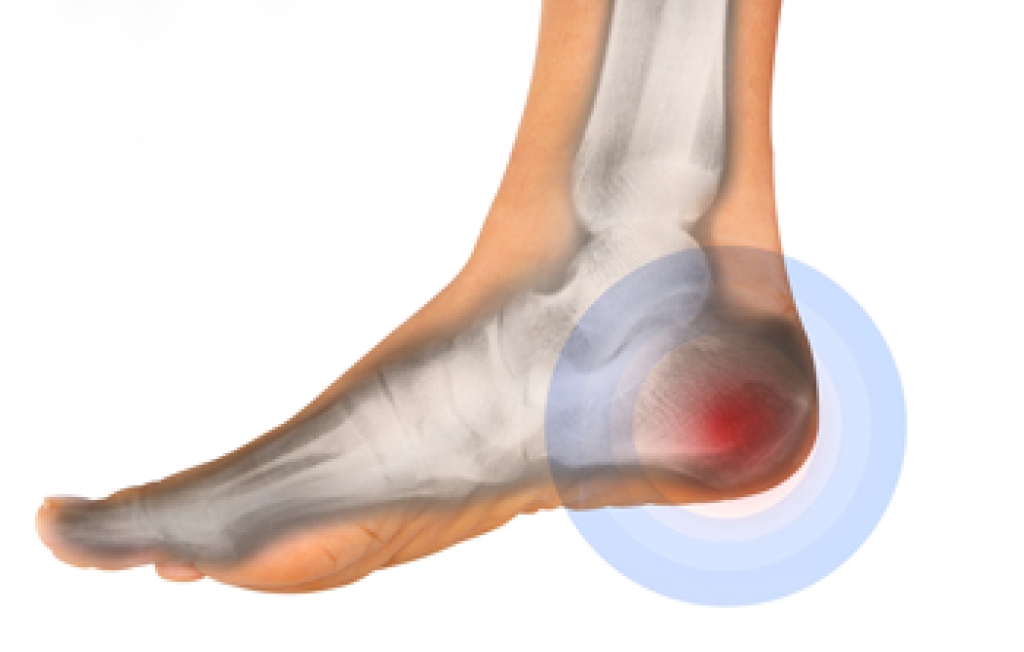

In order to diagnose your bunion, your podiatrist may ask about your medical history, symptoms, and general health. Your doctor might also order an x-ray to take a closer look at your feet. Nonsurgical treatment options include orthotics, padding, icing, changes in footwear, and medication. If nonsurgical treatments don’t alleviate your bunion pain, surgery may be necessary.